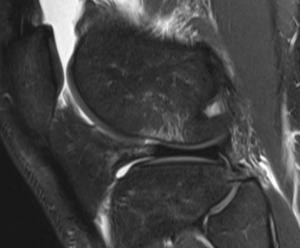

Initial imaging should involve standard radiographs, which are generally unremarkable. However, one should carefully evaluate for a Segond fracture, which is pathognomonic for an ACL tear. This occurs secondary an anterolateral (AL) capsule avulsion from the proximal lateral tibia (Figure 1). An MRI is recommended for evaluation for an ACL tear, meniscal tears, subchondral damage, loose bodies, and bone bruising (Figure 5), which, according to some studies, can all serve as pain generators. Bone bruising occurs in the lateral compartment in over 80% of ACL ruptures, while the medial compartment is involved in varying percentages (14). The literature is conflicting regarding whether these bone bruises are a source of knee pain. This bruising is thought to occur from the tibia and femur impacting one another during a shifting moment. Typically, this occurs in the middle 1/3 of the lateral femoral condyle as well as the posterior 1/3 of the lateral tibial plateau. In two studies, the only factors shown to be linked to bone bruising are injury during non-jumping activities and younger patients (15,16). The severity of bruising has been thought to be related to the amount of impact and possibly future knee function. Chondrocyte damage has been seen histologically with bone bruising and chondral surface thinning in the area of bruising between 1 to 6 years after injury (17,18). With 12-year follow-up in one of these studies, bone bruise changes resolved and there was no difference in pain (16). One study of 672 patients undergoing ACL reconstruction did not link knee pain or symptoms to a bone bruise at index ACL reconstruction, but did link BMI, older age, female sex, LCL injury, MCL injury, medial meniscus status, lateral meniscus status, laxity on Lachman testing, and chondrosis of the medial, lateral, and anterior compartments statistically. However, of these, only concomitant LCL injury was statistically and clinically significant. Importantly, increased knee pain occurring during ACL reconstruction may lead to more difficult rehabilitation as well as more pain at 2 years post-op according to the multicenter study (15).

Figure 5 Sagittal MRI showing a bone bruise after anterior cruciate ligament (ACL) injury.